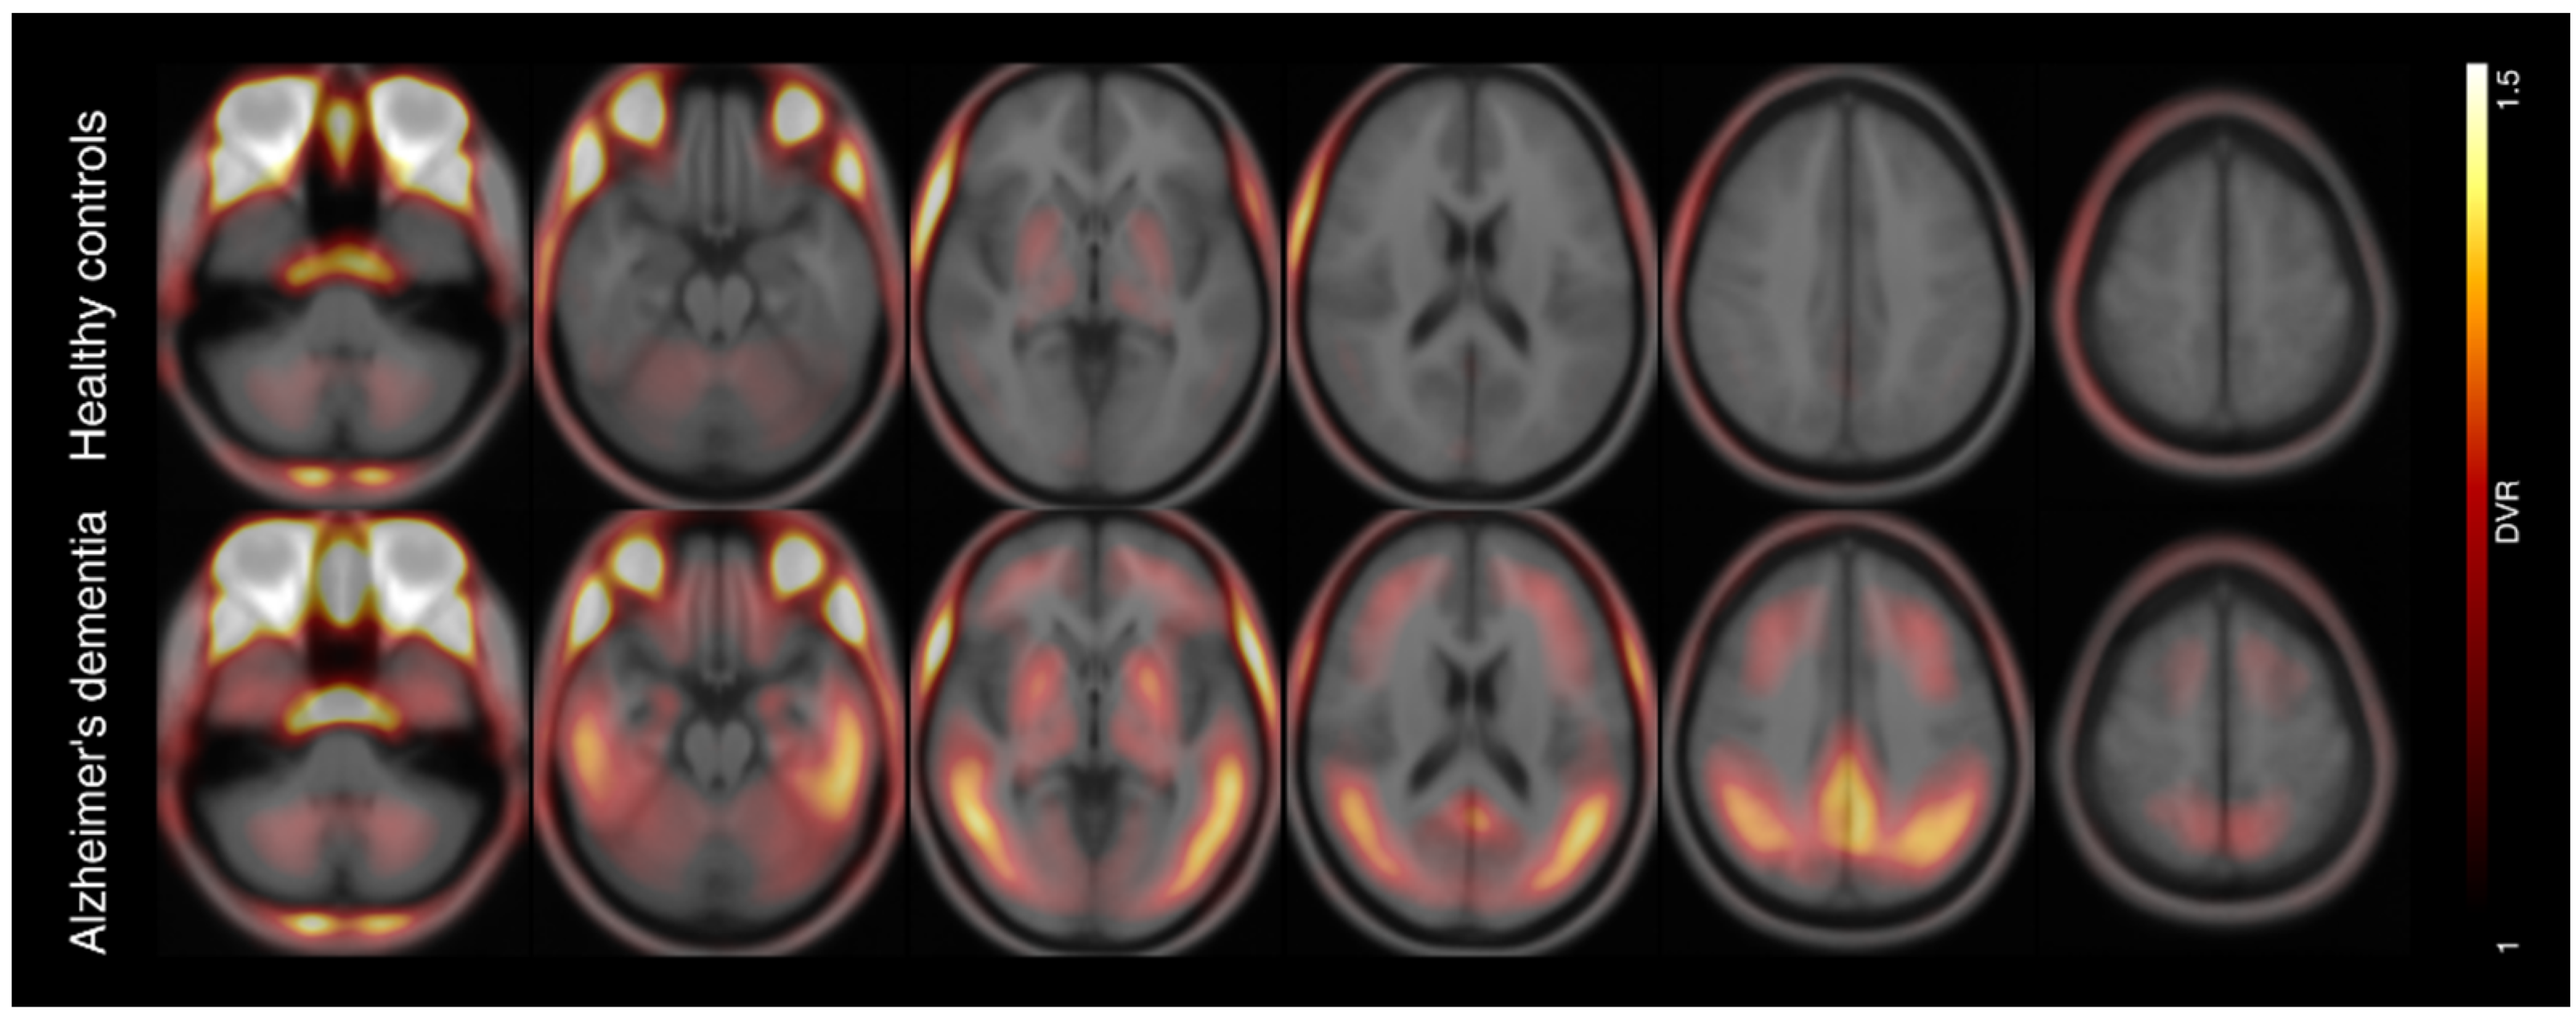

Multicenter 18F-PI-2620 PET for In Vivo Braak Staging of Tau Pathology in Alzheimer’s Disease